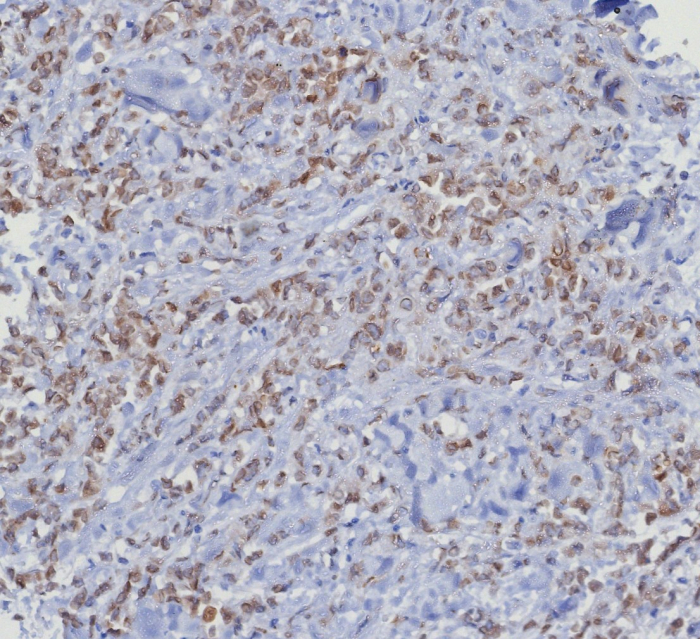

Formulation: Purified Ab WITHOUT BSA and Azide at 1.0mg/ml. Cellular Localization: Nucleus. Cytoplasm. Positive Control: MCF7, HEK293T, cervical carcinoma and liposarcomas., Human urothelial carcinoma, HeLa. Chromosome Location: 12q14.1. Protein Function: Ser/Thr-kinase component of cyclin D-CDK4 (DC) complexes that phosphorylate and inhibit members of the retinoblastoma (RB) protein family including RB1 and regulate the cell-cycle during G(1)/S transition. Phosphorylation of RB1 allows dissociation of the transcription factor E2F from the RB/E2F complexes and the subsequent transcription of E2F target genes which are responsible for the progression through the G(1) phase. Hypophosphorylates RB1 in early G(1) phase. Cyclin D-CDK4 complexes are major integrators of various mitogenenic and antimitogenic signals. Also phosphorylates SMAD3 in a cell-cycle-dependent manner and represses its transcriptional activity. Component of the ternary complex, cyclin D/CDK4/CDKN1B, required for nuclear translocation and activity of the cyclin D-CDK4 complex [The Uniprot Consortium]

| Application: | IHC, WB |